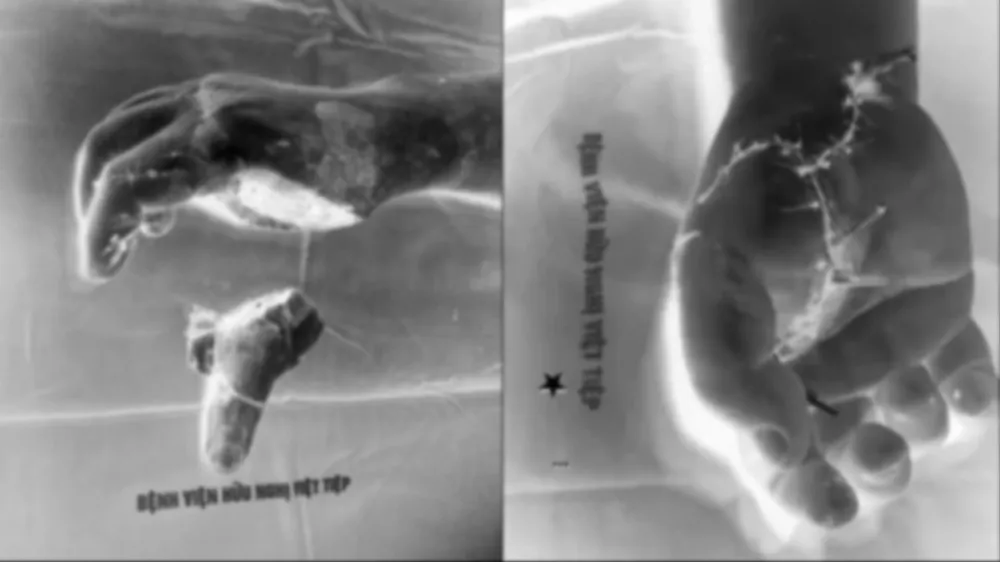

Ngay sau đó, anh Thắng được đưa đến Bệnh viện Hữu nghị Việt Tiệp, kịp thời thực hiện vi phẫu nối ngón tay cái đứt rời, mạch máu, thần kinh, xương và gân cơ. Hiện sức khỏe bệnh nhân đã ổn định, song cần tiếp tục theo dõi do vết thương phức tạp.